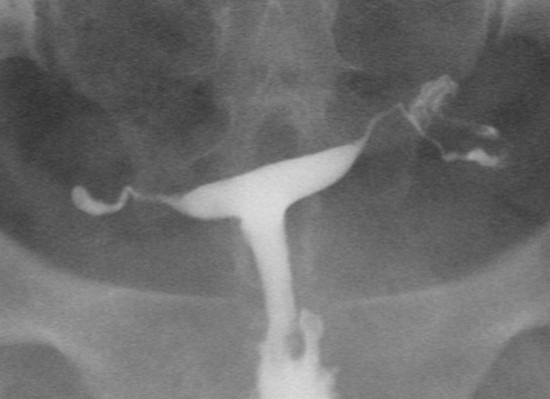

• 2015년 유럽불임학회(ESHRE) P-769 일측 난관수종이 있는 경우, 거의 절반의 경우 반대쪽 난관에 이상이 있어 추가적인 수술이 필요하다.